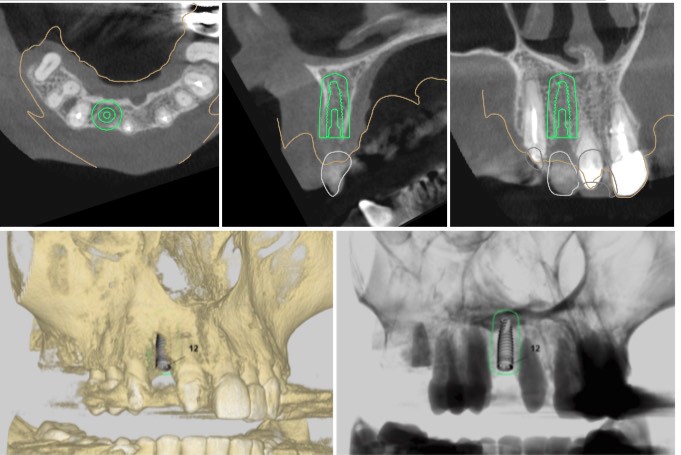

Αρχικά , πραγματοποιούμε μια ακριβή ψηφιακή απεικόνιση του στόματος του ασθενούς με την βοήθεια ακτινογραφιών, αποτύπωσης των δοντιών και φωτογραφιών.

Στη συνέχεια, μελετούμε ψηφιακά το οστό των γνάθων (επάρκεια και ποιότητα), τα ανατομικά στοιχεία των γνάθων (νεύρα, ιγμόρειο άντρο) και αποφασίζουμε τι είδους εμφύτευμα θα χρησιμοποιήσουμε (μήκος, διάμετρος) ώστε να γίνει η ιδανική προσθετική αποκατάσταση, σύμφωνα με το σχήμα των παρακείμενων δοντιών και την σύγκλειση.

Τέλος, κάνουμε ψηφιακή εκτύπωση ενός χειρουργικού νάρθηκα, τον οποίο χρησιμοποιούμε την ημέρα της επέμβασης. Με αυτόν τον τρόπο, η τοποθέτηση των εμφυτευμάτων γίνεται γρήγορα και με απόλυτα προβλέψιμο αποτέλεσμα.